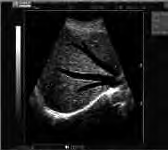

Świadczenie usług medycznych …

Jakie struktury anatomiczne uwidoczniono na obrazie USG?

Ilustracja do pytania 33

A. Pęcherz moczowy z kamieniami.

B. Ciężarna macica z czterema płodami.

C. Nerka lewa ze złogami.

D. Pęcherzyk żółciowy z kamieniami.